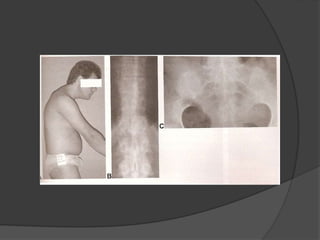

Deformidade

 Hipercifose “do começo ao fim” da

coluna e hiperflexão quadris

 Lombar > Torácica > Cervical

 RX panorâmico em perfil, com o

pescoço numa posição neutra e

incluindo quadris em extensão máxima;

linha mento-superciliar (normal 0) →

Importante para o planejamento

cirúrgico